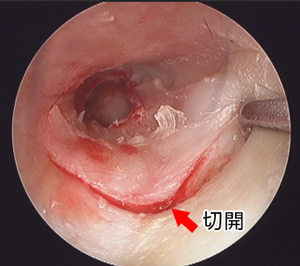

○内視鏡下手術による好酸球性副鼻腔炎の治療術前CTでみられた副鼻腔の炎症(灰色)が、術後CTでは正常(黒色)になっています

○咽頭・喉頭がんに対する経口的切除術(TOVS & ELPS)